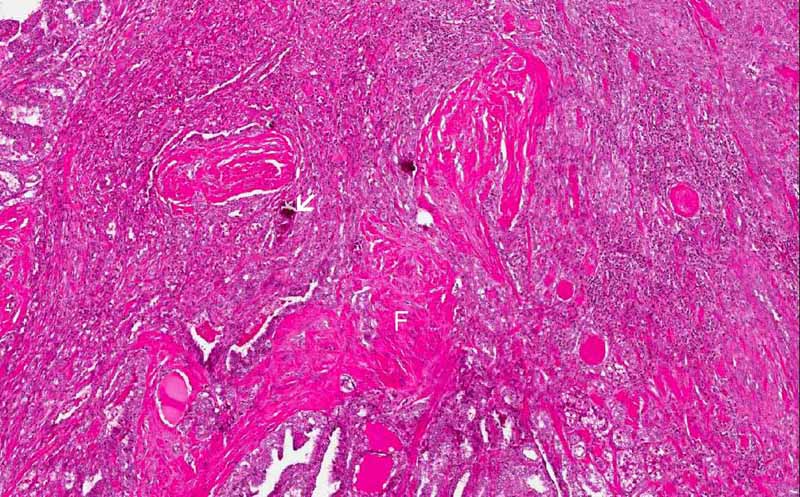

Area 1: Note the irregular margin of the tumor.

Area 4: Fibrosis (F) and calcifications (C) are characteristic features of thyroid papillary carcinoma. These calcifications can exists as amorphous depositioins or round, concentric psammoma bodies.

• The tumor is an roughly nodular blue lesion (outlined by the arrows) and with irregular margin (Area 1).

• Fibrosis and calcifications are common in papillary thyroid carcinoma (Area 4).